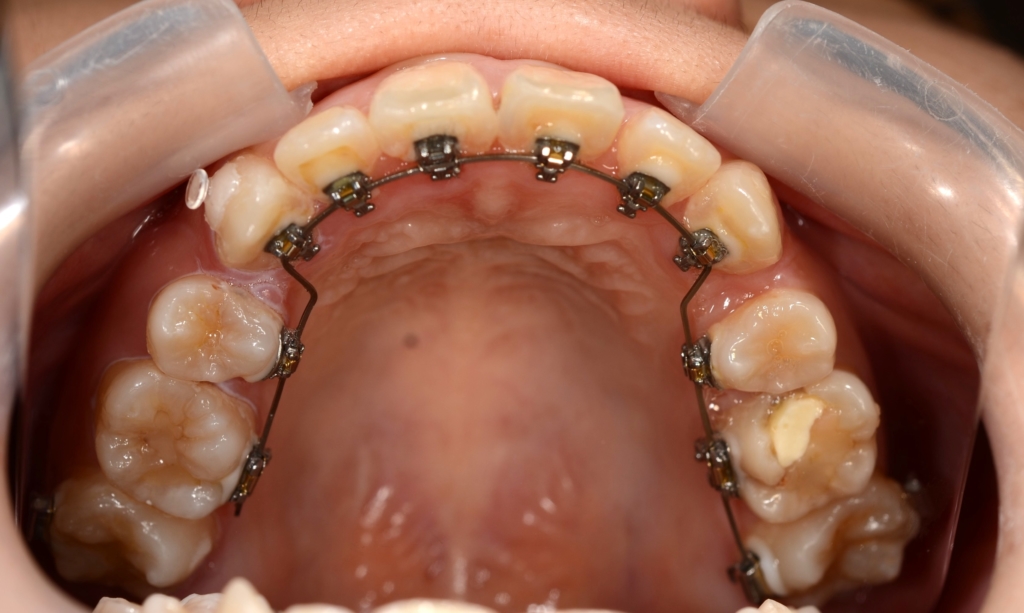

マルチブラケットシステム(ハーフリンガル type)で矯正を開始。

上下の左右の奥歯を1本ずつ計4本抜歯(4番目の第一小臼歯を抜きました)

1.上下の左右の奥歯を抜歯をしてスペースを作り、前歯をきれいに並べる

2.残る隙間分は、できるだけ前歯を奥へ引っ込める